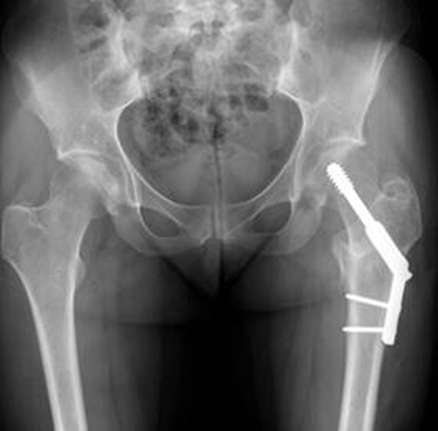

Hip Fractures

In 2024, Maine Health Orthopedics completed a two-year long quality project at Maine Medical Center Portland that worked to reduce the time to surgery for hip fracture patients. Hip fracture surgery is one of the most common orthopedic trauma surgeries in Maine, with about one a day done at MMC Portland. This project stemmed from a multi-center collaborative study with Stanford. Delayed surgery (>24-48 hours) for hip fracture patients is associated with higher morbidity, mortality, and overall cost, but determinants of delayed surgery are varied and context dependent. As such, improvement strategies are ideally specific to the identified driver of delay in a given context.

Working with Stanford staff, semi-structured interviews were completed with stakeholders involved in all aspects of hip fracture care to identify determinants affecting time to surgery for hip fracture patients. Then, working with leaders from Emergency Medicine, Internal Medicine, Anesthesia and many more, Dr. Camuso’s team worked to address these determinants. Overall, the project was successful, reporting a decreased time to surgery for hip fracture patients.